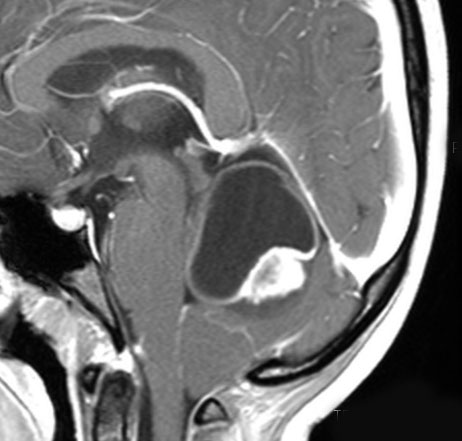

中脳視蓋毛様細胞性星細胞腫 tectal glioma(詳しくはここをクリック)

中脳視蓋グリオーマとして知られるものです。この腫瘍は基本的には,初回手術で全摘出できるのですが,現実的には,技術的に難しすぎるので部分摘出で終えることが多いでしょう。この子は,15歳の時に閉塞性水頭症のために,頭痛,嘔吐,意識障害,瞳孔不同となりました。開頭部分摘出術と第3脳室開窓術で回復して,その後にカルボプラチンとビンクリスチンの化学療法を受けました。でも腫瘍増大が止められずに,発症1年後に54グレイ30分割の放射線治療を受けています。さらにその半年後くらいから再増大しましたが,スードプログレッションと考えられました。のう胞性拡大が止まらず,発症3年後にまた再開頭手術で亜全摘出しました。